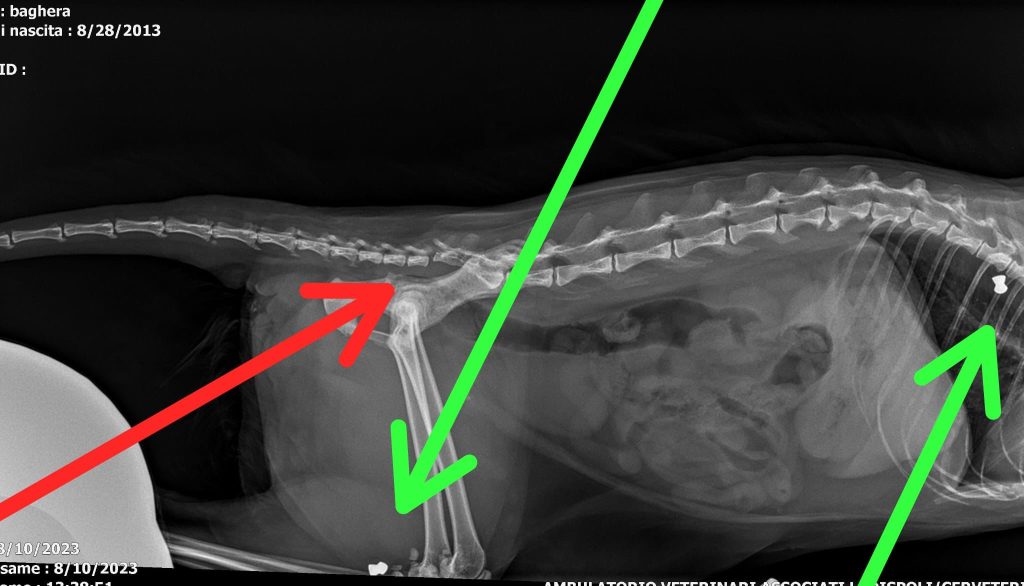

Si è verificato uno spiacevole episodio nella zona Madonna dei Canneti, Saturno, Via Ferretti a Cerveteri. Sono stati colpiti dei gattini con una pistola ad aria compressa, causando danni fisici ad una gattina anziana di 10 anni. Nella lastra si è scoperto avere la coda rotta e diversi proiettili nel corpo.